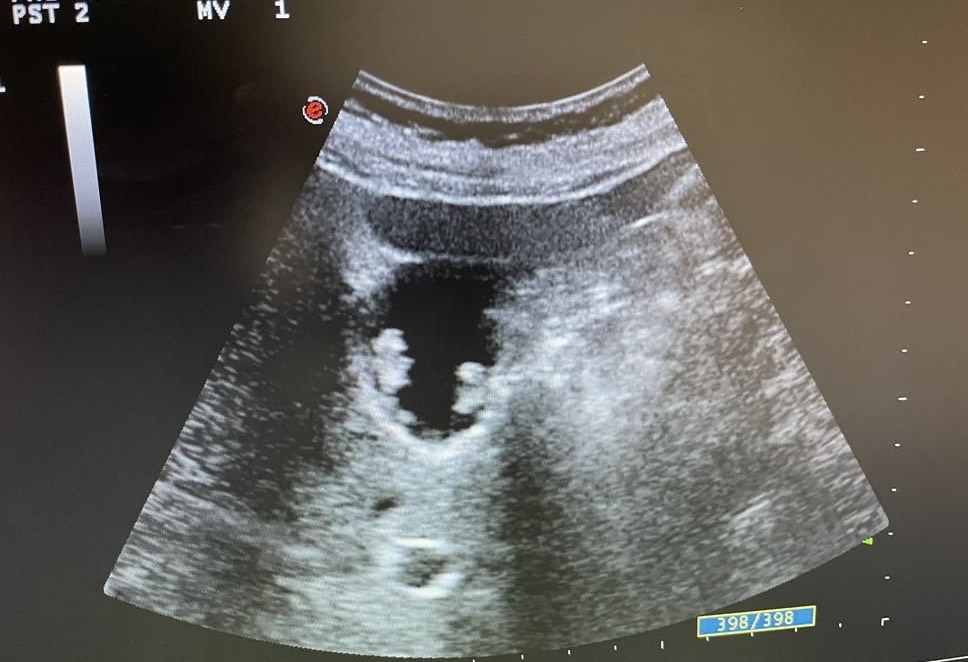

Mentalmente describí las lesiones, se trata de lesiones múltiples hiperecogénicas y adheridas a la pared vesicular y que no producen sombra posterior.

Confirmé que no se trataba de colelitiasis sino que en mi opinión eran múltiples pólipos vesiculares y alguno de ellos cercano a 1 cm de diámetro, sin poder descartar malignidad con la ecografía, por lo que solicité un TC abdominal que informó de un único pólipo vesicular de 6 mm.

Desde la consulta de cirugía se solicitó ecografía reglada y control en 6 meses que informó de múltiples engrosamientos nodulares en relación con pólipos (más de 10), los de mayor tamaño alcanzan 9 mm de grosor máximo. Alitiasica.

Se decidió colecistectomía.